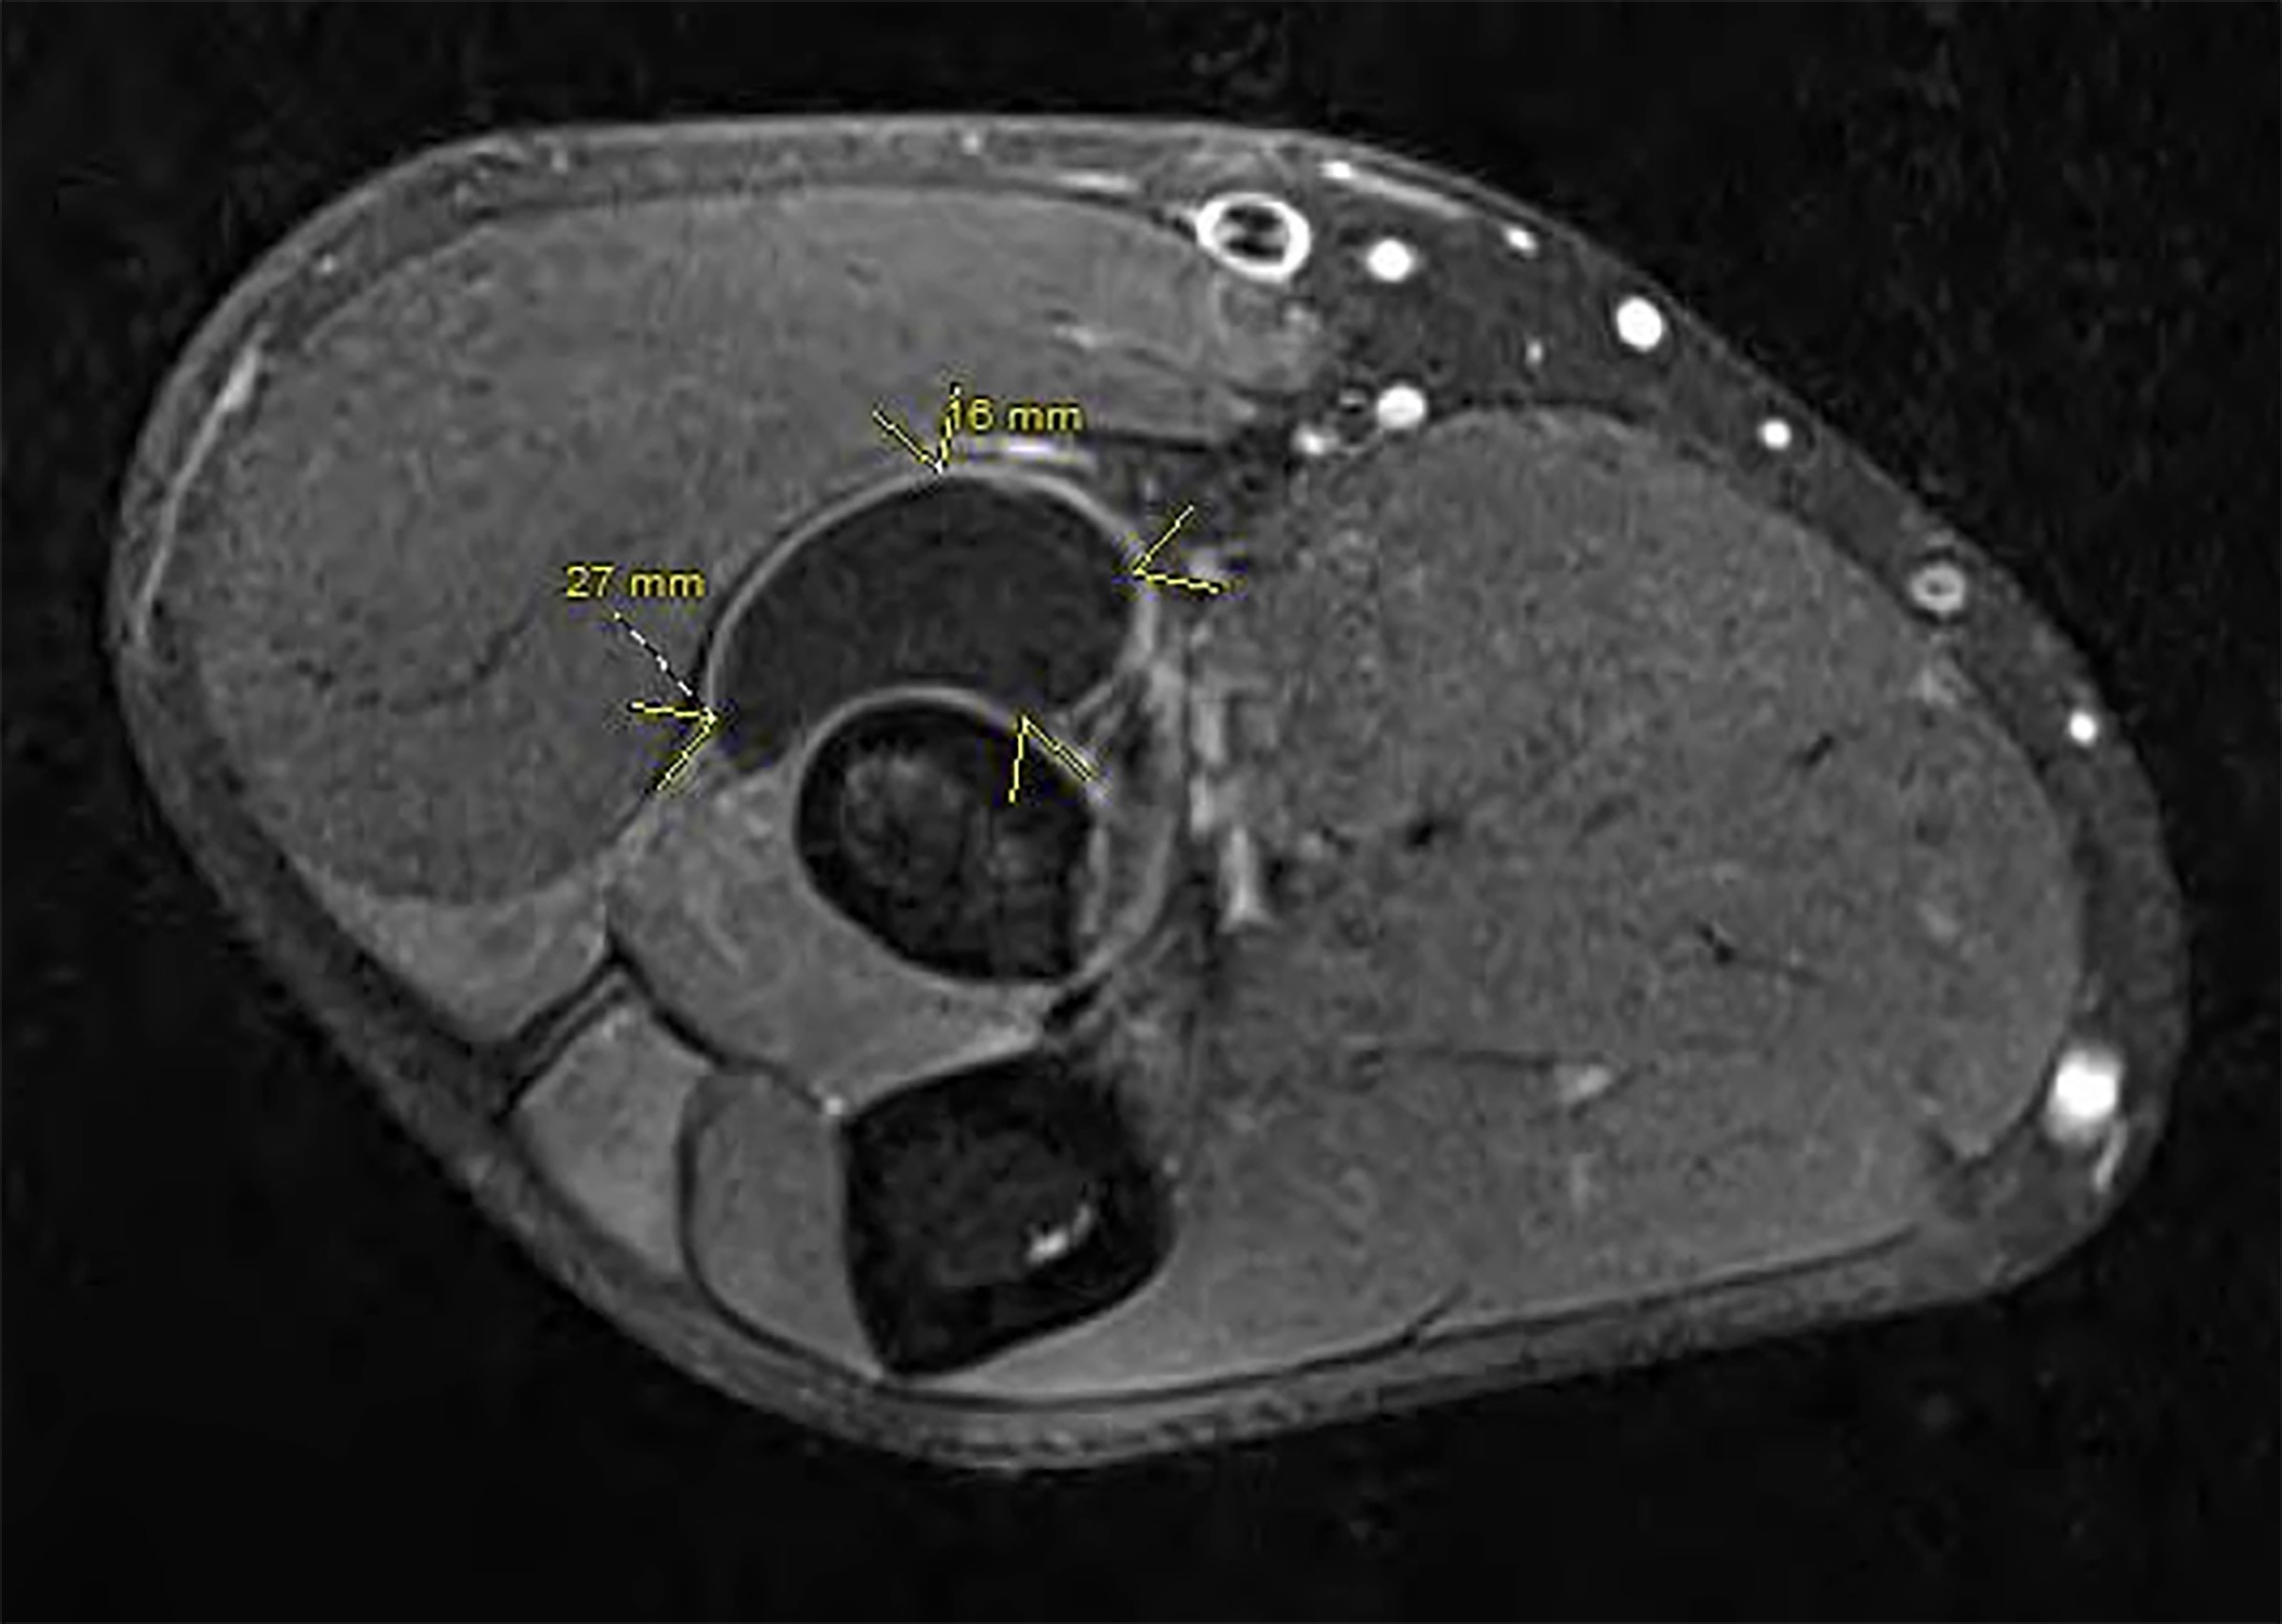

A 42-year-old, right-hand dominant male presented with several months of progressive right upper extremity motor weakness. The patient first noticed weakness and then the complete loss of extension of the long finger and ring finger, followed by the loss of extension of the small finger, and eventually weakness of the thumb and index finger extension (Figure 1). The patient’s wrist extension was intact, and there were no palpable masses or inciting traumatic events. Electromyography (EMG) and nerve conduction studies (NCS) were ordered and demonstrated posterior interosseous nerve (PIN) involvement. Magnetic resonance imaging (MRI) of the right forearm showed a well-circumscribed mass over the radial head. The patient was taken to the operating room for excision of the mass. Intraoperatively a 44 mm x 27 mm x 16 mm lipoma located deep against the PIN, causing obvious clinical PIN narrowing, was excised. All branches of the radial nerve were spared, and a complete decompression of the PIN was performed. The patient had progressive and continued recovery of finger extension postoperatively. (Figure 1)

The best tools to discern the etiology of radial nerve palsy are an astute history and physical exam, as the loss of motor function depends on the level of radial nerve involvement. In this case, the patient had intact elbow and wrist extension, indicating intact innervation to the triceps muscles and wrist extensors (ECRB, extensor carpi radialis longus ) which effectively ruled out a brachial plexus or proximal radial nerve injury. The patient’s progressive loss of finger extension and absence of distal sensory symptoms pointed to a progressive process distal to the origin of the PIN. At this point, adjunct studies such as MRI and radiographs are indicated to rule out underlying masses, fractures, dislocations, and foreign bodies. In this case, the MRI demonstrated a sizeable lipoma (Figure 2, Figure 3). Suspected radial nerve paralysis from a penetrating injury follows a slightly different algorithm than in penetrating trauma and should be explored urgently. In these cases, adjunct imaging such as MRI or arteriograms may be useful prior to exploration whereas electrodiagnostic studies prior to exploration are unnecessary.4 Early EMG and NCS are unable to differentiate between nerve injuries that will or will not heal spontaneously and should be reserved for persistent nerve paralysis beyond 6 to 8 weeks.1 By 12 weeks, the presence of motor unit potentials can differentiate injuries that will require surgery or heal spontaneously.

The differential diagnosis for forearm masses is broad. Reported masses causing PIN compression include lipomas, liposarcomas, ganglion cysts, intraneural hemangiomas, and tumors of nerve origin.2,5 As previously mentioned, an MRI serves as a useful adjunct in determining the cause of nerve palsy and may assist with diagnosing masses when detected. Importantly, MRIs prior to surgery can help distinguish between benign and malignant masses, which may alter surgical planning, margins, and reconstruction. Although effective in diagnosing masses, an MRI is not definitive. A recent study on upper extremity lesions found an overall sensitivity of MRI of 75% compared to lesion pathology after excision, with improved radiologic diagnosis of ganglions and lipomas compared to malignant lesions.6 Pertinent to this case, lipomas characteristically demonstrate MRI signal characteristics identical to subcutaneous fat, which include hyperintense T1 and T2 signals with hypointense short-TI inversion recovery (STIR) signal (Figure 2, Figure 3).6 Heterogeneity within the lesion should raise the possibility of liposarcoma as a possible diagnosis. In contrast, ganglion cysts typically present with hypointense T1 signal and hyperintense T2 and STIR signals. An MRI with gadolinium contrast is useful for detecting and differentiating between possible vascular lesions.